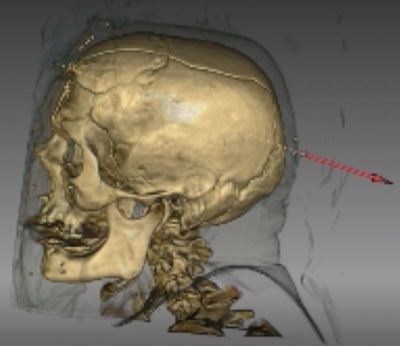

L'imagerie forensique est devenue, au fil des ans, une discipline très prisée des médecins légistes pour les assister dans leur discipline. Des reconstructions en trois dimensions d’images scanographiques acquises post-mortem permettent, par exemple, de reconstituer les trajets lésionnels provoqués par des balles, ce qui constitue un type de pièces à conviction à présenter devant une cour de justice.

Ce travail se base, en plus des données démographiques, sur les principales données recueillies à l’autopsie et au scanner, en aveugle l’un de l’autre, notamment le nombre de systèmes lésionnels, leur orientation, le calibre des projectiles et les résidus de tir, le bilan lésionnel détaillé ou la détection des épanchements. Sur le plan radiologique, les chercheurs ont établi un protocole d'acquisition précis comportant un topogramme de face en décubitus dorsal, les bras le long du corps, suivi d’une première acquisition cervico-crânienne sans injection de produit de contraste, reconstruites en traitements osseux et parenchymateux cérébral, puis d’une deuxième acquisition sans injection de produit de contraste, en coupes millimétriques, de la région cervicale à l’extrémité des pieds, reconstruites en traitements osseux, médiastinal et parenchymateux pulmonaires.

Une revue scanographique exhaustive de tous les organes traversés par le projectile

Les trajectoires balistiques sont ici évaluées au scanner dans les 3 plans de l’espace, selon la méthode utilisée par les médecins légistes dans les rapports d’autopsie, et d'après des éléments sémiologiques comme les défauts dans le revêtement cutané, associés à des bulles d’emphysème sous-cutanées par exemple. Le trajet hématique se manifeste, d'autre part, par une hyperdensité linéaire au sein des masses musculaires ou du parenchyme cérébral. Un trajet bulleux dans les organes pleins et les poumons sont également des critères d'évaluation précis, de même que le descriptif lésionnel de l’encéphale aux pieds, en analysant différents axes artériels et veineux (aorte thoracique et abdominale, troncs artériels supra-aortiques, mésentère, veine cave inférieure), ainsi que chaque organe, chaque segment osseux, avec latéralisation systématique et recherche d’épanchement au contact des organes pleins intra-abdominaux.

Les trajectoires balistiques sont ici évaluées au scanner dans les 3 plans de l’espace, selon la méthode utilisée par les médecins légistes dans les rapports d’autopsie, et d'après des éléments sémiologiques comme les défauts dans le revêtement cutané, associés à des bulles d’emphysème sous-cutanées par exemple. Le trajet hématique se manifeste, d'autre part, par une hyperdensité linéaire au sein des masses musculaires ou du parenchyme cérébral. Un trajet bulleux dans les organes pleins et les poumons sont également des critères d'évaluation précis, de même que le descriptif lésionnel de l’encéphale aux pieds, en analysant différents axes artériels et veineux (aorte thoracique et abdominale, troncs artériels supra-aortiques, mésentère, veine cave inférieure), ainsi que chaque organe, chaque segment osseux, avec latéralisation systématique et recherche d’épanchement au contact des organes pleins intra-abdominaux.

Cette étude a inclus 225 cas, ce qui lui confère une solidité significative. Au final, et comme on pouvait s'y attendre, le scanner et l’autopsie semblent concordants dans bien des cas, notamment sur le nombre et l'orientation des systèmes lésionnels. L'autopsie semble supérieure sur les résidus de tirs cutanés tandis que le scanner l'emporte sur la détection des épanchements. Reste que, dans cette pratique, il existe des limites à l'utilisation du scanner, notamment pour identifier précisément le calibre des projectiles ou lorsque les membres se trouvent en dehors du champ d’acquisition. Cette étude, qui est soumise pour publication dans l'International Journal of Legal Medicine, permet d'établir une complémentarité suffisante entre le scanner et l'autopsie classique dans les cas de traumatismes balistiques fatals.

Cette technologie confère une aide précieuse aux médecins légistes pour déterminer les causes d'un décès, par l'étude d'un trajet balistique, l'évaluation de l'état d'un squelette après un accident ou l'identification, par angioscanner post-mortem, des conséquences d'une hémorragie massive. Elle est également déterminante pour l'identification des corps après une catastrophe naturelle ou industrielle. L'Institut Médico-légal du CHU de Tours a fait le choix, en fin d'année 2018, de s'équiper d'un scanner de dernière génération afin d'améliorer la qualité du service rendu à la justice en matière d'autopsie médico-légale. Il s'est tourné, pour ce faire, vers Fujifilm et a fait l'acquisition de son nouveau scanner FCT Speedia 64 barrettes. Il est devenu ainsi le premier institut médico-légal français à s’équiper d’un scanner Fujifilm.